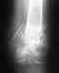

Re: многооскольчатый перелом обеих костей в/з правой голени. Не срастается

Проблема понятна. В принципе, может срастись и в положении как есть. Но лучше бы пересинтезировать хоть тем же стержнем, но с устранением все смещений. Технически это вполне выполнимо, надо только знать и уметь делать все необходимые элементы операции.